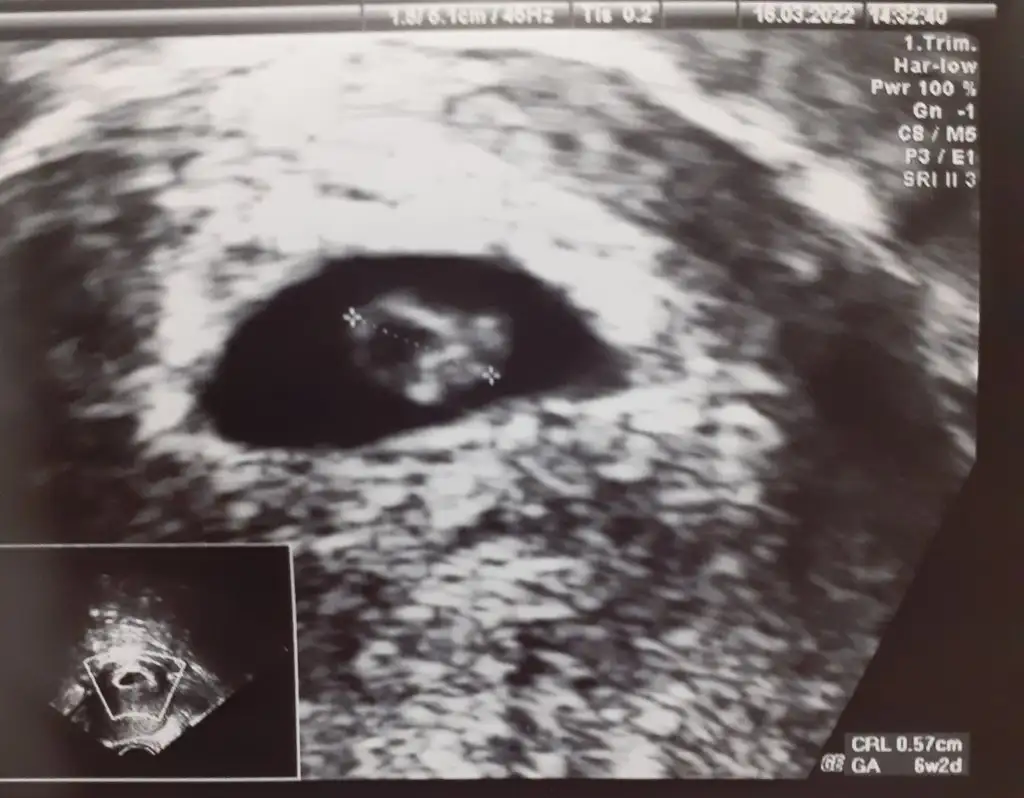

Salı günü ikili test var doktor bakarım cinsiyete demiştine zaman öğreneceksin

ayhh hadi inşallah sen ne istiyorsun pekiSalı günü ikili test var doktor bakarım cinsiyete demişti

kuzucum nub un yatay bak

Yaa hadi bakalım hayırlısıyla inşallahkuzucum nub un yatay bakbir prenses geliyor

gönlünden geçen olsunYaa hadi bakalım hayırlısıyla inşallahdoktor erkek olabilir ama net değil kızlarda da bu çıkıntı olabiliyor dedi öğrenince haber veririm